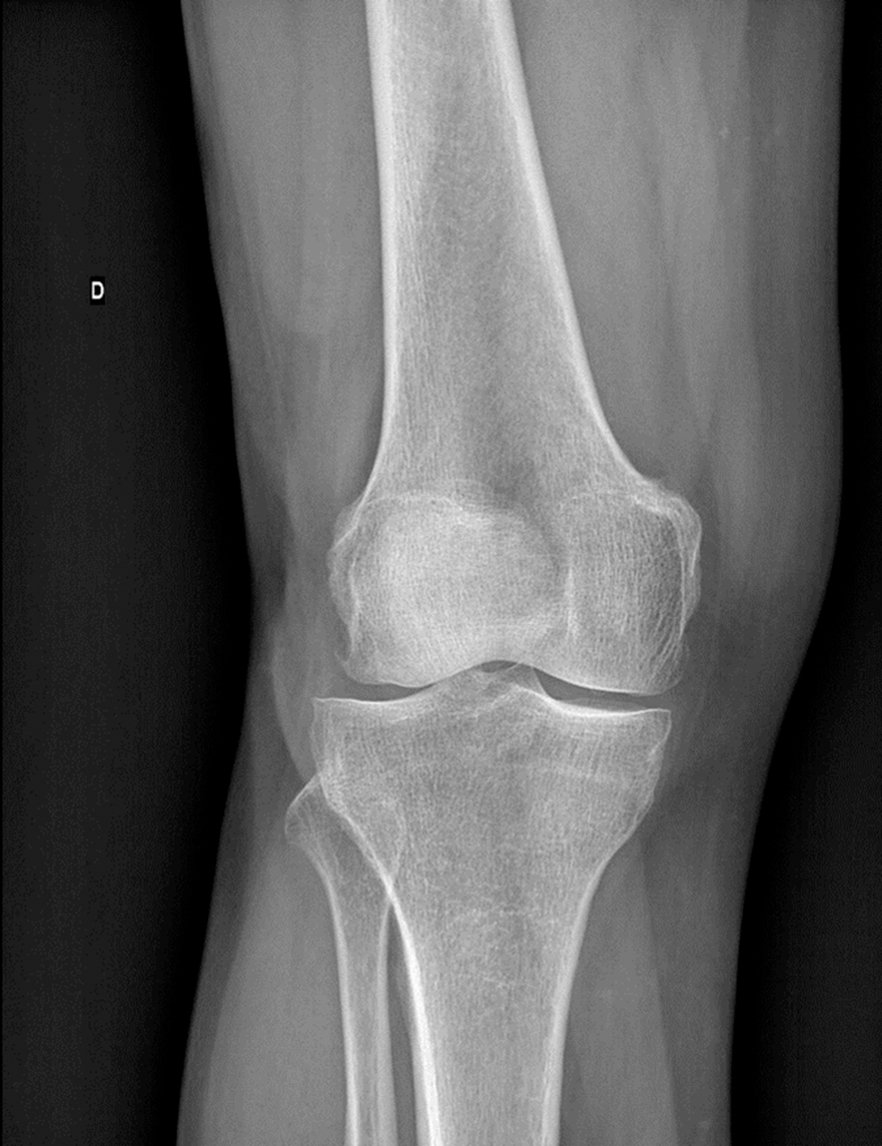

Une radiographie du genou de face est disponible.

Figure 1 (Salomé Abdellaoui, La Revue du Praticien)

La radiographie du genou de face est normale, sans pincement ni érosion, et on ne visualise pas de calcifications méniscales, ce qui permet d’écarter une chondrocalcinose articulaire et un diagnostic de gonarthrose.